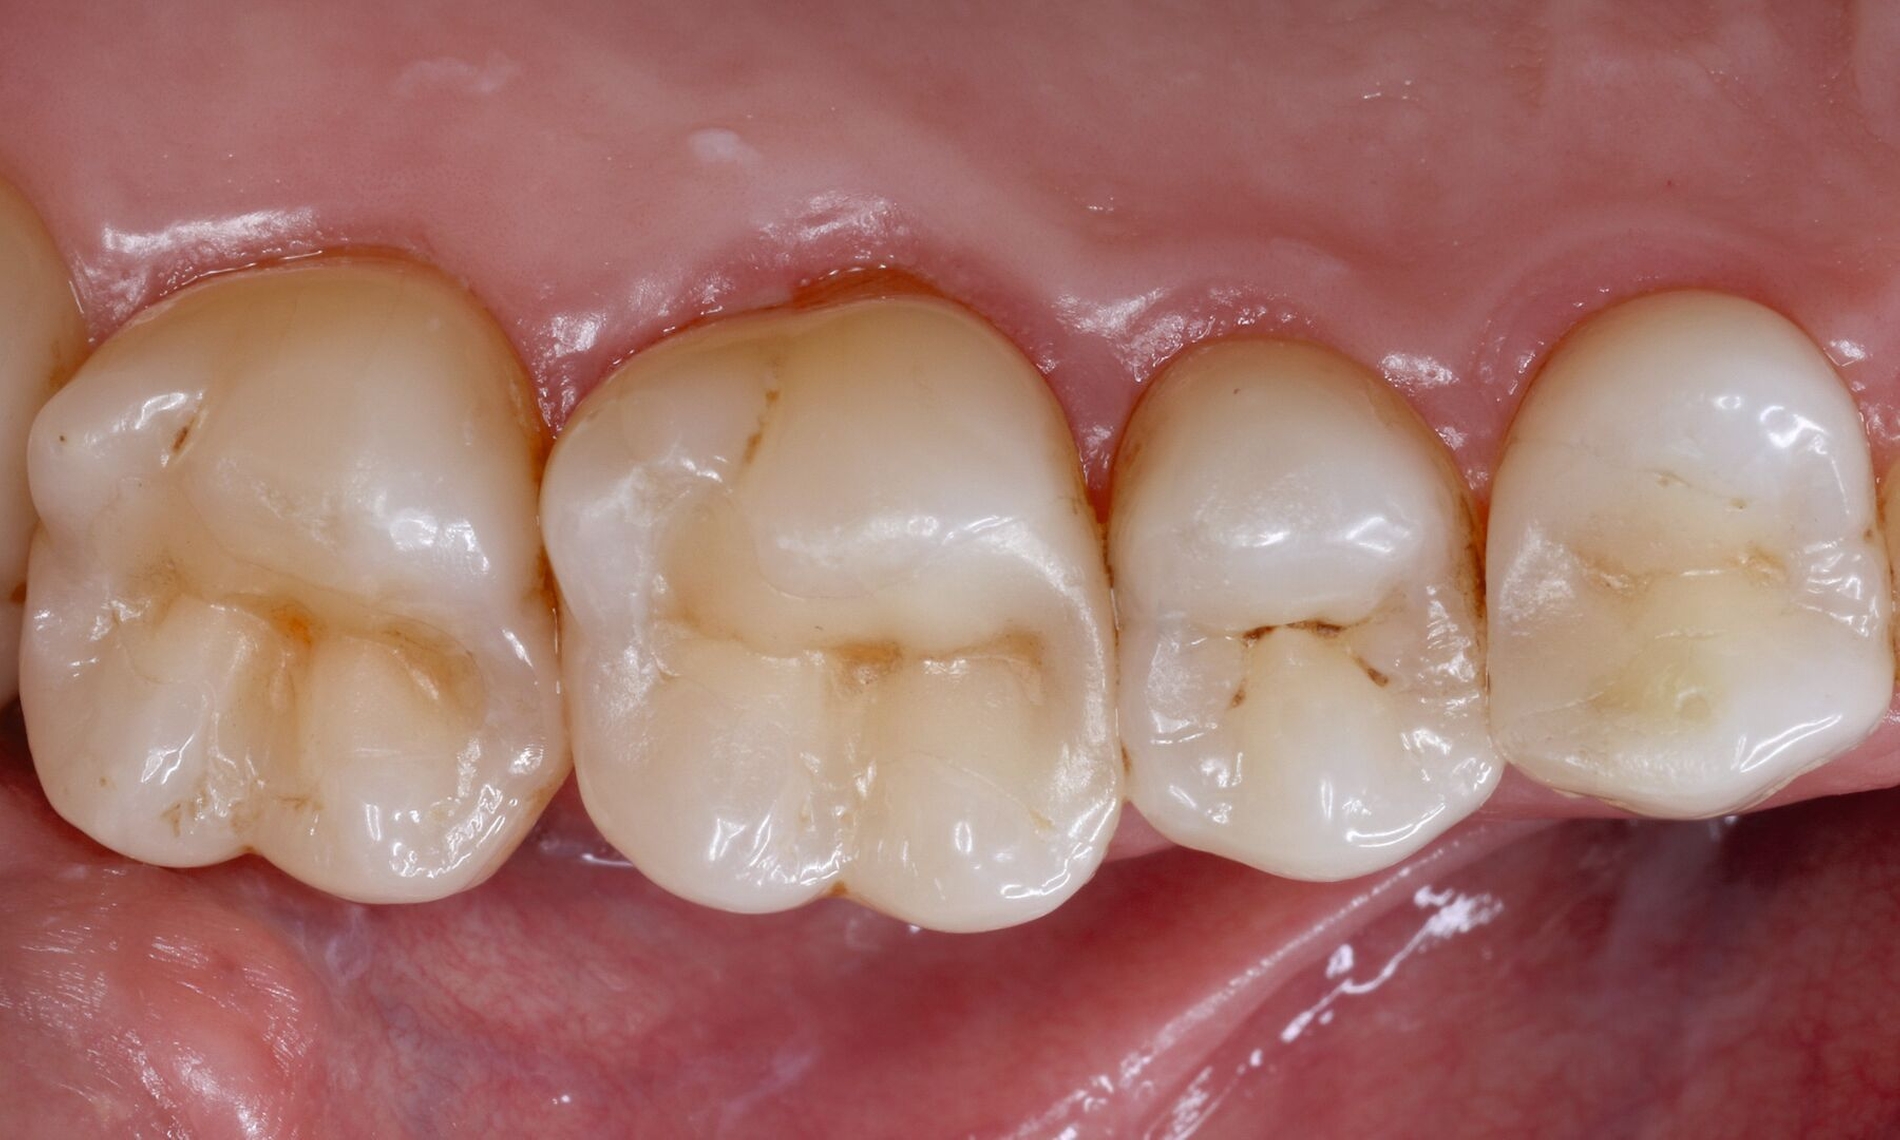

Darüber hinaus muss man bei der Erörterung konventioneller Zementunterfüllungen realistischerweise immer in Betracht ziehen, dass niemals jedes einzelne Dentinkanälchen von Zement bedeckt sein wird und somit selbstverständlich immer zusätzlich mit einem Adhäsivsystem (für Schmelz und Dentin) gearbeitet werden muss. Dies gilt vor allem für die Approximalbereiche, in denen der Abstand zur Pulpa oft geringer ist als okklusal (Abbildung 1).

Eine besondere Situation stellt die Caries profunda dar. Hier gibt es hinreichend Evidenz, dass unterhalb einer Restdentindicke von 300 μm zum einen die Gefahr besteht, dass kurzkettige Monomere das Dentin durchdringen und Biomineralisationsprozesse der Odontoblasten stören können [Galler et al., 2011; Schmalz et al., 2001]. Praktisch viel wichtiger ist jedoch ein rein geometrisches Problem: Bondet man eine Kompositrestauration im Dentin so nahe an der Pulpa, bilden sich neben der für die Dentinhaftung verantwortlichen Hybridschicht auch Harzzotten (Resin Tags), die bis zu 300 μm in das Dentin eindringen (Abbildung 2). Das würde bedeuten, dass sich die Tags praktisch am Eingang der Pulpa befinden, was weder klinisch noch anatomisch sinnvoll erscheint. Gleiches gilt für pulpanahe Bereiche bei Kronenfrakturen. Insbesondere bei Kindern sind die Dentintubuli noch weit offen und das Dentin ist an diesen Stellen hoch permeabel [Krastl et al., 2021].

Für solche tiefen Areale existieren zwei unterschiedliche Lösungsansätze: Entweder man exkaviert einfach weniger aggressiv [Schwendicke et al., 2013] oder man appliziert ausschließlich in diesen Bereichen kleine Mengen klassischer „Cp-Medikamente“ oder Kalziumsilikatzemente [Schmidt et al., 2020] im Sinne einer kleinen Unterfüllung zur Blockade der „Tags“ [European Society of Endodontology, 2019]. Der weniger tief exkavierte Rest der Kavität wird aber auch hier vollständig mit einem Adhäsivsystem versiegelt und nicht mit einer konventionellen Zementunterfüllung [Arandi et al., 2020; European Society of Endodontology, 2019]. Eine korrekte Indikationsstellung für die Applikation eines Cp-Materials ist jedoch wichtig, da diese Materialien die Gesamthaftung in der restlichen Kavität reduzieren können [Frankenberger et al., 2021]. Die adhäsive Dentinversiegelung stellt heute den wirksamsten Schutz des Pulpa-Dentin-Komplexes dar (Abbildungen 3 und 4) [Arandi et al., 2020]. Das Risiko, dass die Pulpa dadurch einen irreversiblen Schaden erleidet, ist äußerst gering und minimal im Vergleich zum Schädigungspotenzial eines Diamantschleifers, der bei Amalgam und Gold oftmals „im Gesunden“ statt rein minimalinvasiv verwendet werden musste [Olmez et al., 1995; Schweikl et al., 2017].